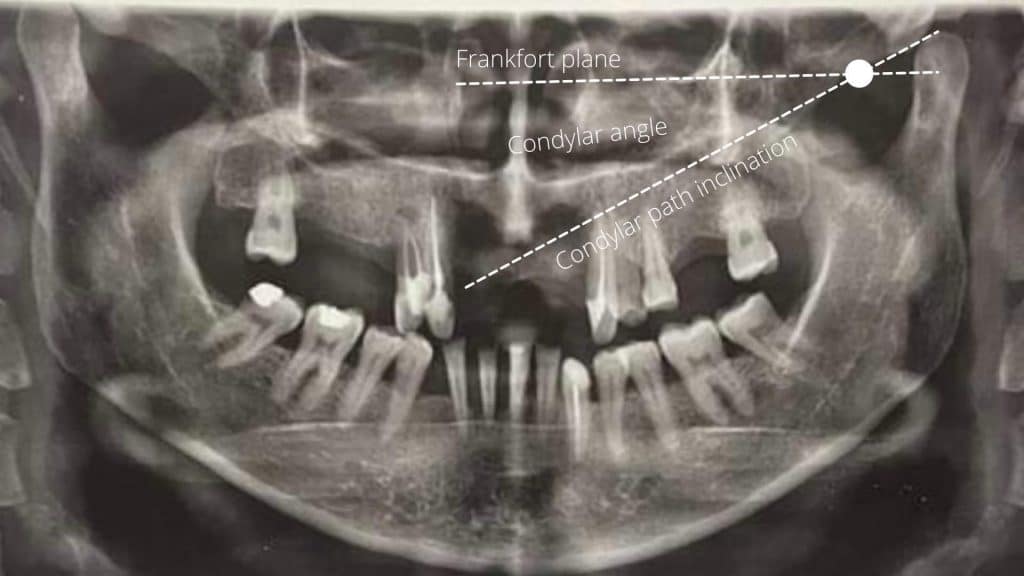

The steepness of posterior tooth anatomy and anterior teeth axial inclination is determined by condylar guidance angle ( angle between frankfort plane and condylar path inclination )